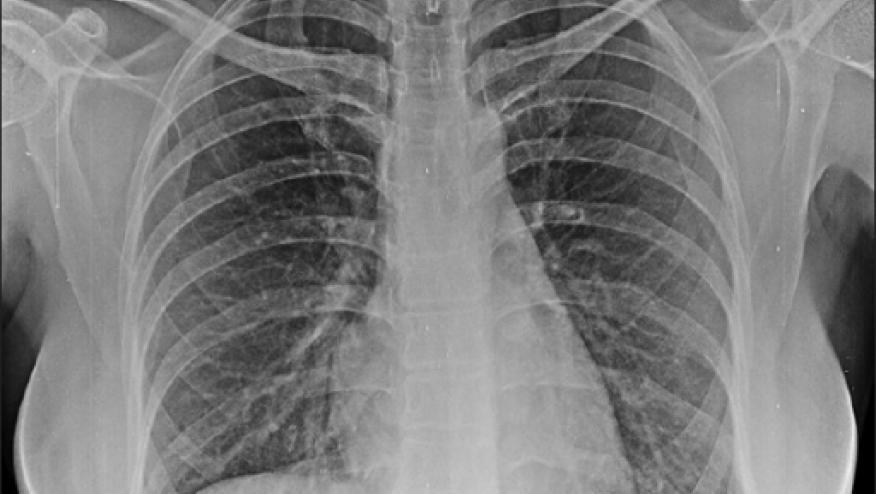

A TriNetX EHR study shows that psoriatic arthritis (PsA), but not Psoriasis (PsO), patients are at increased risk for interstitial lung disease (ILD).

These data suggest a need for respiratory monitoring in PsA patients, in a manner similar to RA assessments.